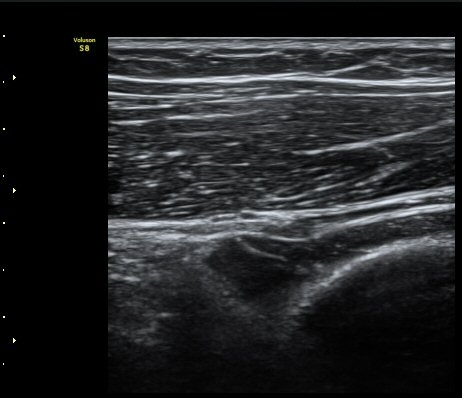

[ÆÈ²ÞÄ¡] Å״Ͻº¿¤º¸¿ì(¿Ü»ó°ú¿°)¿¡ µ¿¹ÝµÈ ¿ä°ñ½Å°æ Èİñ°£ºÐÁö º´Áõ 2

ÃÊÀ½ÆÄ °Ë»ç